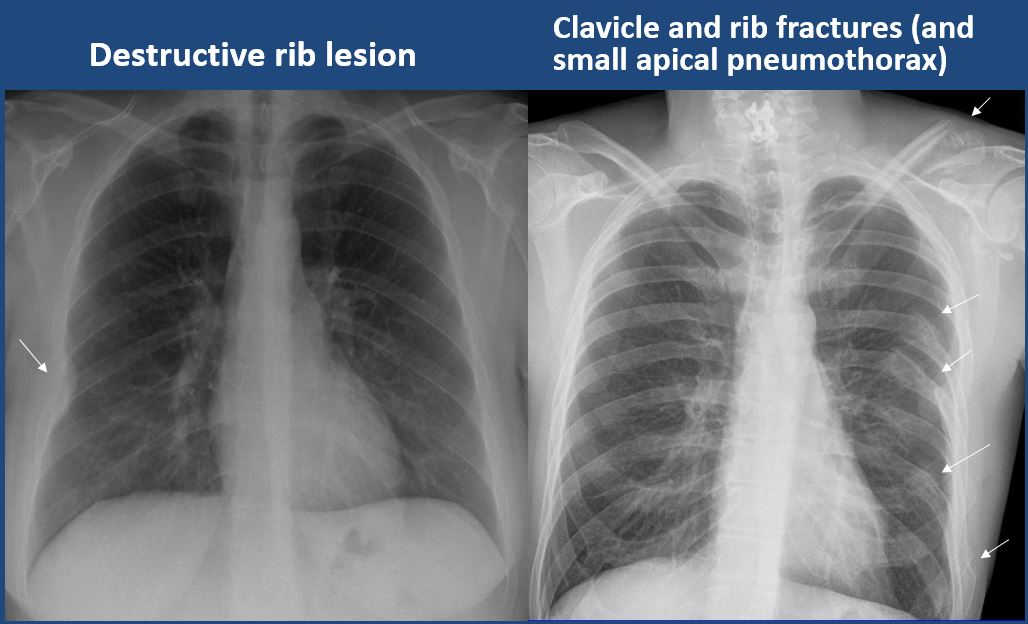

There is a pneumothorax, hydro/pneumothorax, or hemo/pneumothorax. [Yes/No]

The ribs, clavicles, shoulder, spine, or other visualized bones are abnormal. [Yes/No]